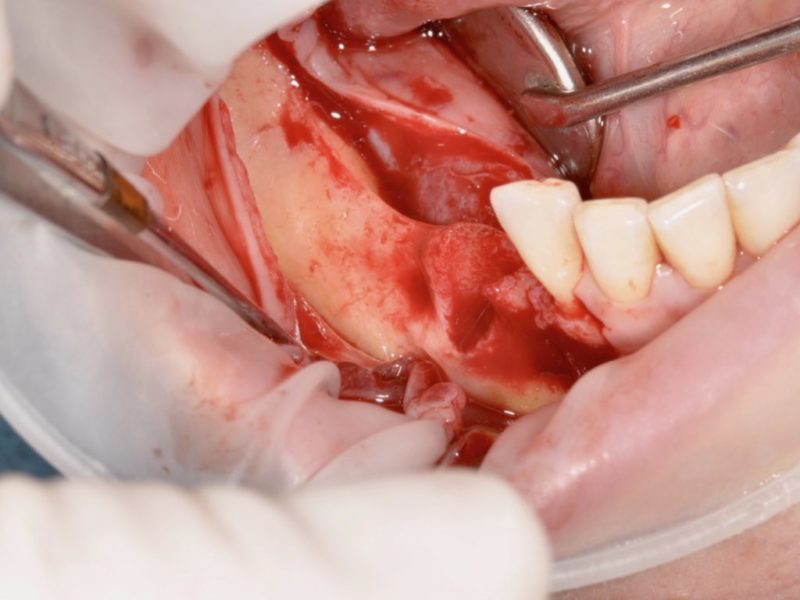

This patient came to us with a vertical bone defect. The patient has a reabsorbed saddle that is not suitable for implant insertion, so it was decided to perform a first surgery with the insertion of bone regeneration material and wait for it to heal before proceeding with the insertion of B&B Dental implants. From a first radiological examination before surgery we evaluated the situation, the vertical bone defect becomes evident and from the clinical check up we can classify the soft tissue with a thin gingival morphotype. The surgery required the opening of s full thickness flap with release incisions and total detachment from the whole ridge. The titanium T-barrier has been modeled and adapter to the anatomy of the ridge, then it has been filled with bone regeneration material and fixed with 4 screws for osteosynthesis. In addition we applied a collagen T-barrier membrane on top.

After 4 months we performed a second surgery to remove the titanium grid. The soft tissued are more keratinized and we could notice the restoration of bone volumes that are now suitable for the insertion of implants. We then performed during this stage the insertion of 3P and EV line implants based on bone density.